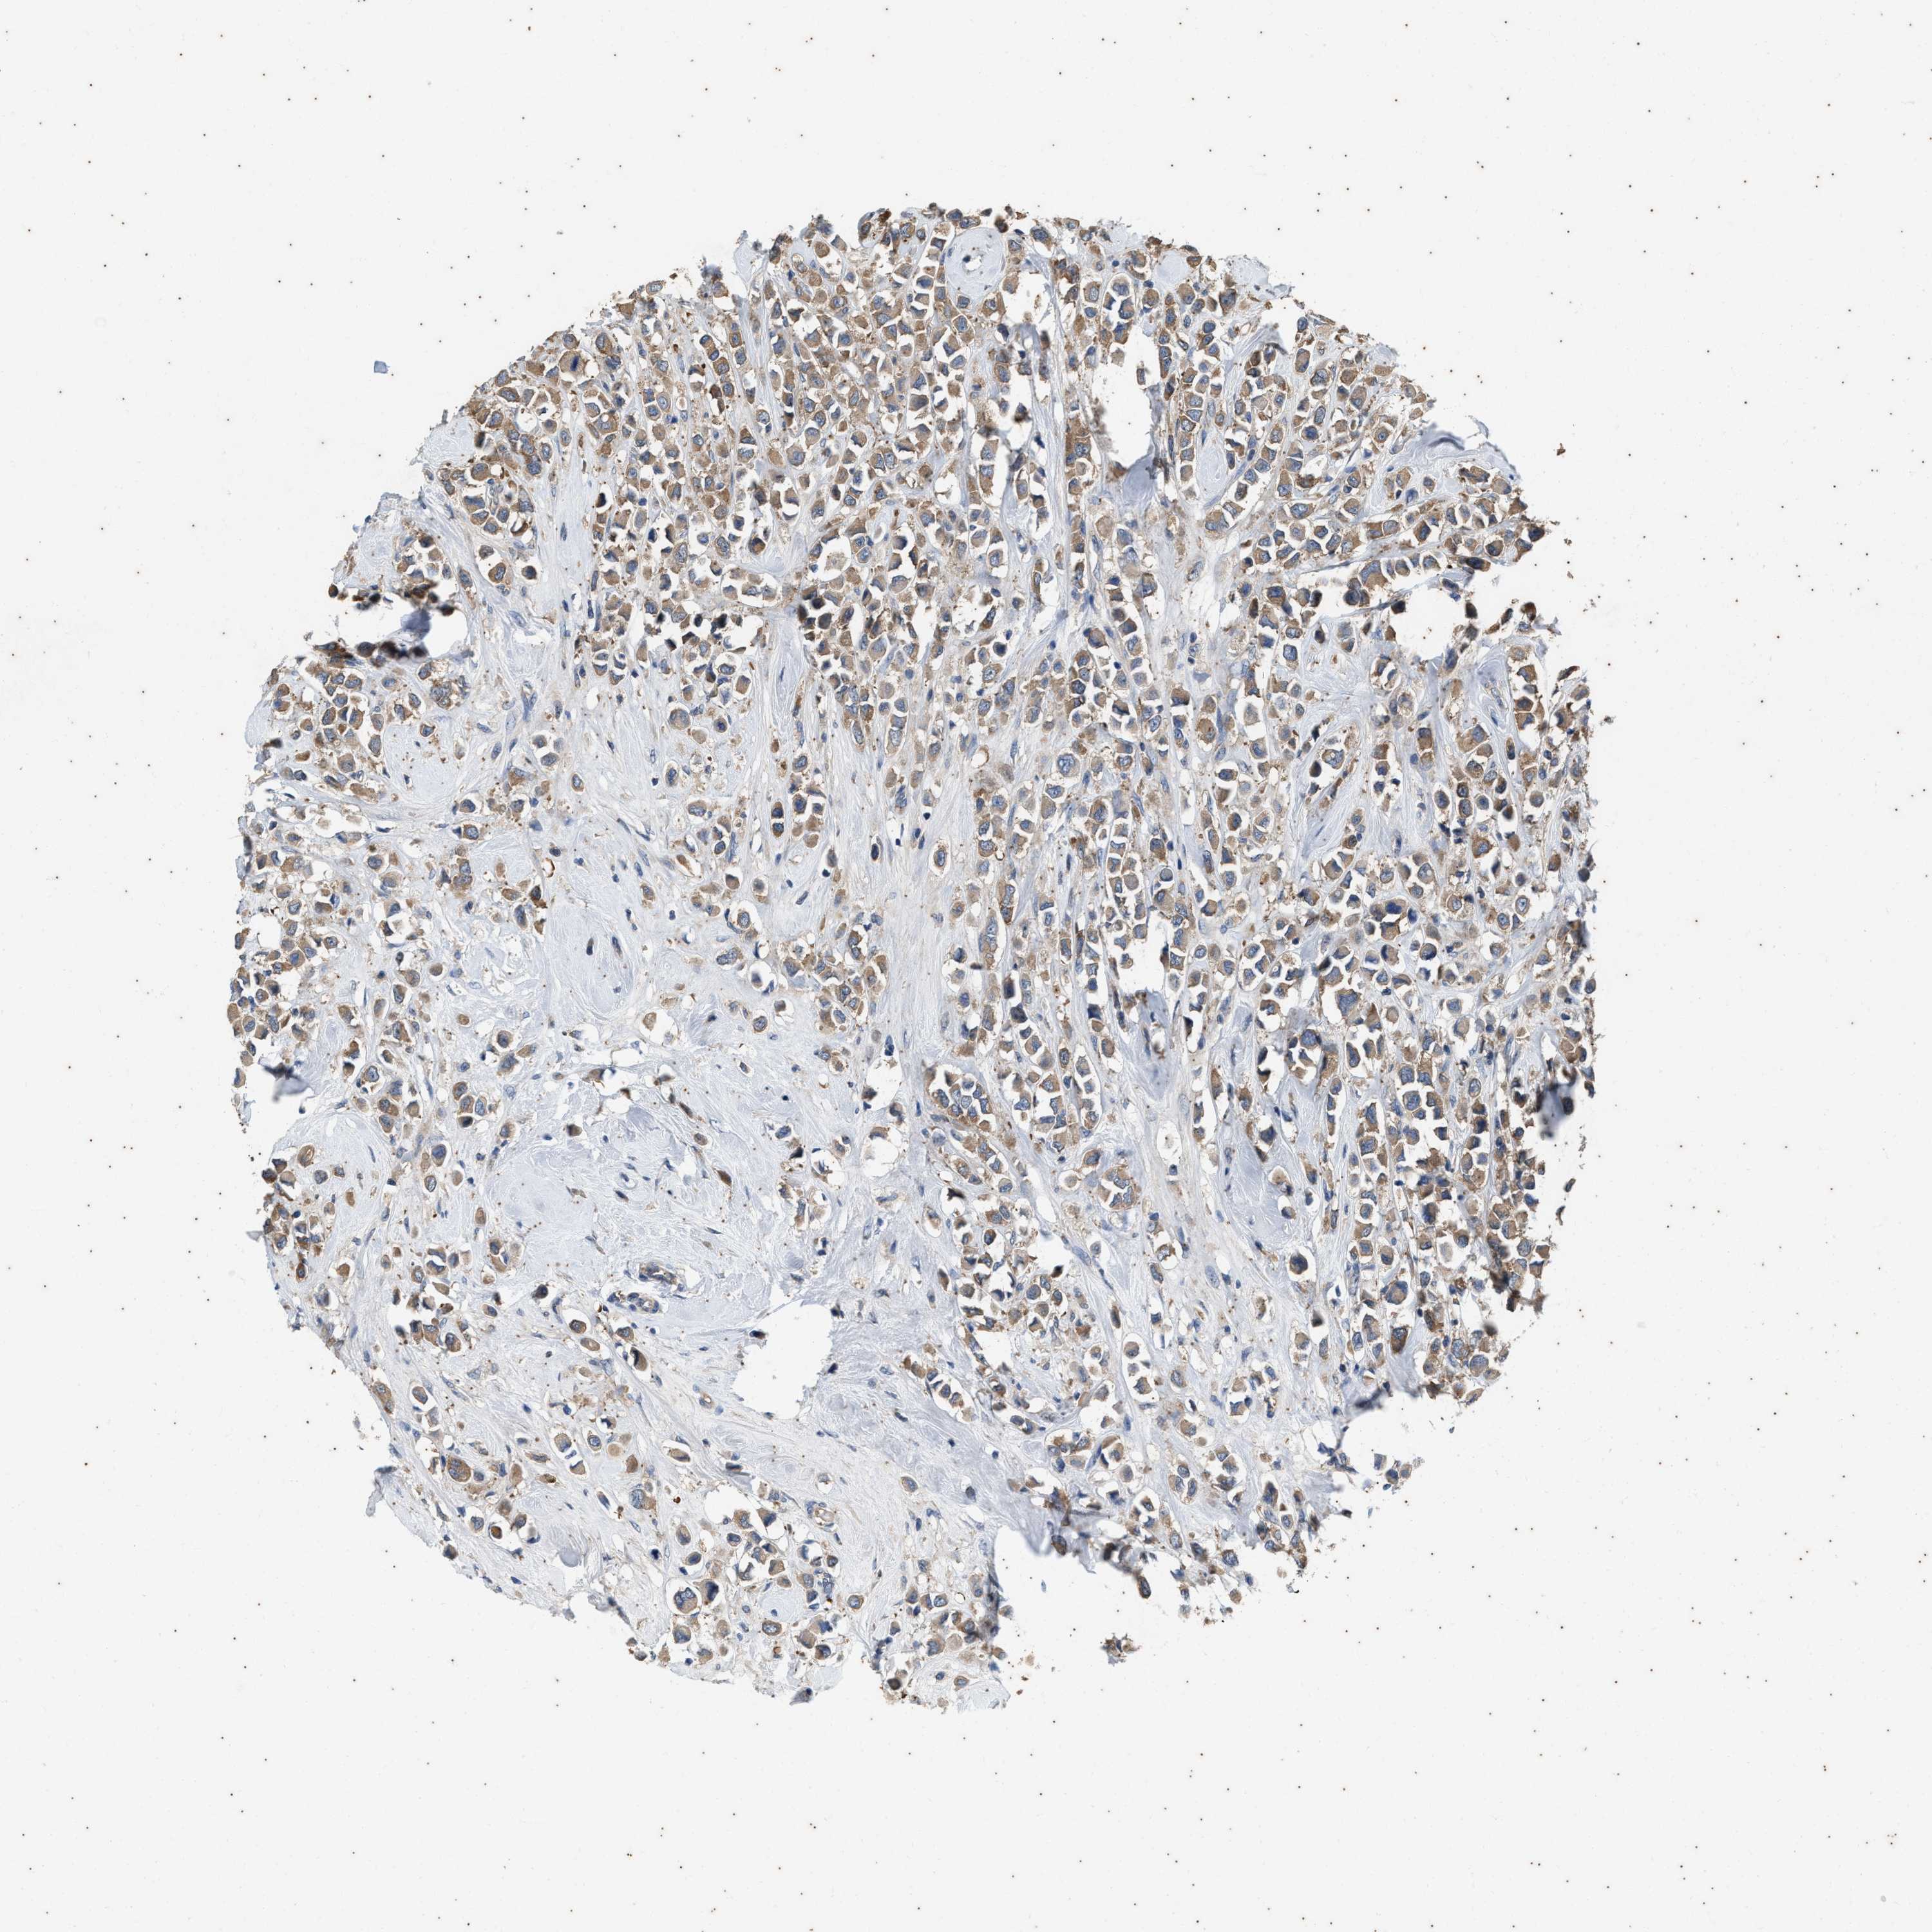

CANCER BREAST CANCER Show tissue menu

BRCA TCGA BRCA VALIDATION PROTEIN EXPRESSION